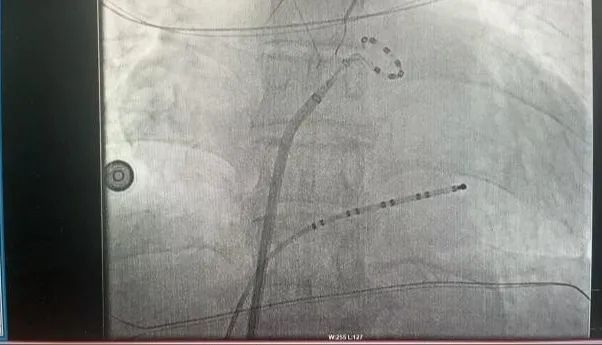

此次手術患者均為持續性房顫患者,由延安大學咸陽醫院吳棟梁院長、心律失常專家劉雄濤副院長帶領介入團隊開展,安全高效、圓滿完成手術,手術過程患者全程清醒,術中自訴感覺良好,無痛苦感受。術后患者的心律恢復并維持了竇律,目前恢復情況良好,無任何并發癥出現。